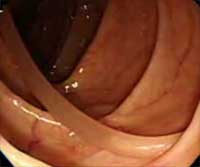

大腸内視鏡検査で発見された、腸内潜むワーム

- 2008.4.6

テラノーバ症(アニサキス症)にかかった患者の体内

マックのフィレオフィッシュから寄生虫「テラノーバ」が見つかっちゃったということで、寄生虫テラノーバが引き起こすアニサキス症にかかっちゃうとどうなっちゃうのかという映像を、もう一度復習して見てみることにしようそうしようになりました。実際発見されたものは冷凍により死んでいたのでこんな風にはなりませんが、それでも生魚を食べるチャンスが多い日本人の場合にはやっぱり注意が必要なのです。タラ、サケ、マス、サバ、スルメイカは特に注意ということです。

この寄生虫は、冷蔵庫程度の低温では長い時間生きており、また通常用いる程度のわさびや酢、醤油では死なないそうですが、加熱するか、−20℃以下の低温で5〜6時間冷凍すれば死んでしまうのだそうです。そんなことより何度か紹介しているにもかかわらず、アニサキスをついうっかりアニキサス(兄貴挿す)と誤字してしまうパルモもなにかに感染している疑いが高いのだと思います何の病気?ねえ阿部さんなんの病気?